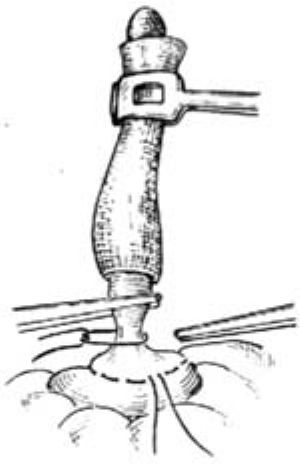

12.6 6.荷包縫合

提起闌尾,圍繞闌尾根部在距闌尾根部0.5~0.8cm處的盲腸壁上(根部粗者距離應較大),作一荷包縫合,暫不收緊。注意每針均應深及肌層,但勿穿入腸腔內[圖1 ⑸]。

12.7 7.結紮闌尾根部

用一把直止血鉗在距闌尾根部0.5cm處壓榨一下(用後棄去此污染的直鉗),防止結紮時縫線滑脫。隨即用4號絲線在壓痕處結紮,用止血鉗靠闌尾夾住結紮線,貼鉗剪去線頭。再用直止血鉗在結紮線遠端0.4cm處夾緊闌尾[圖1 ⑹]。

圖1 ⑹結紮闌尾根部